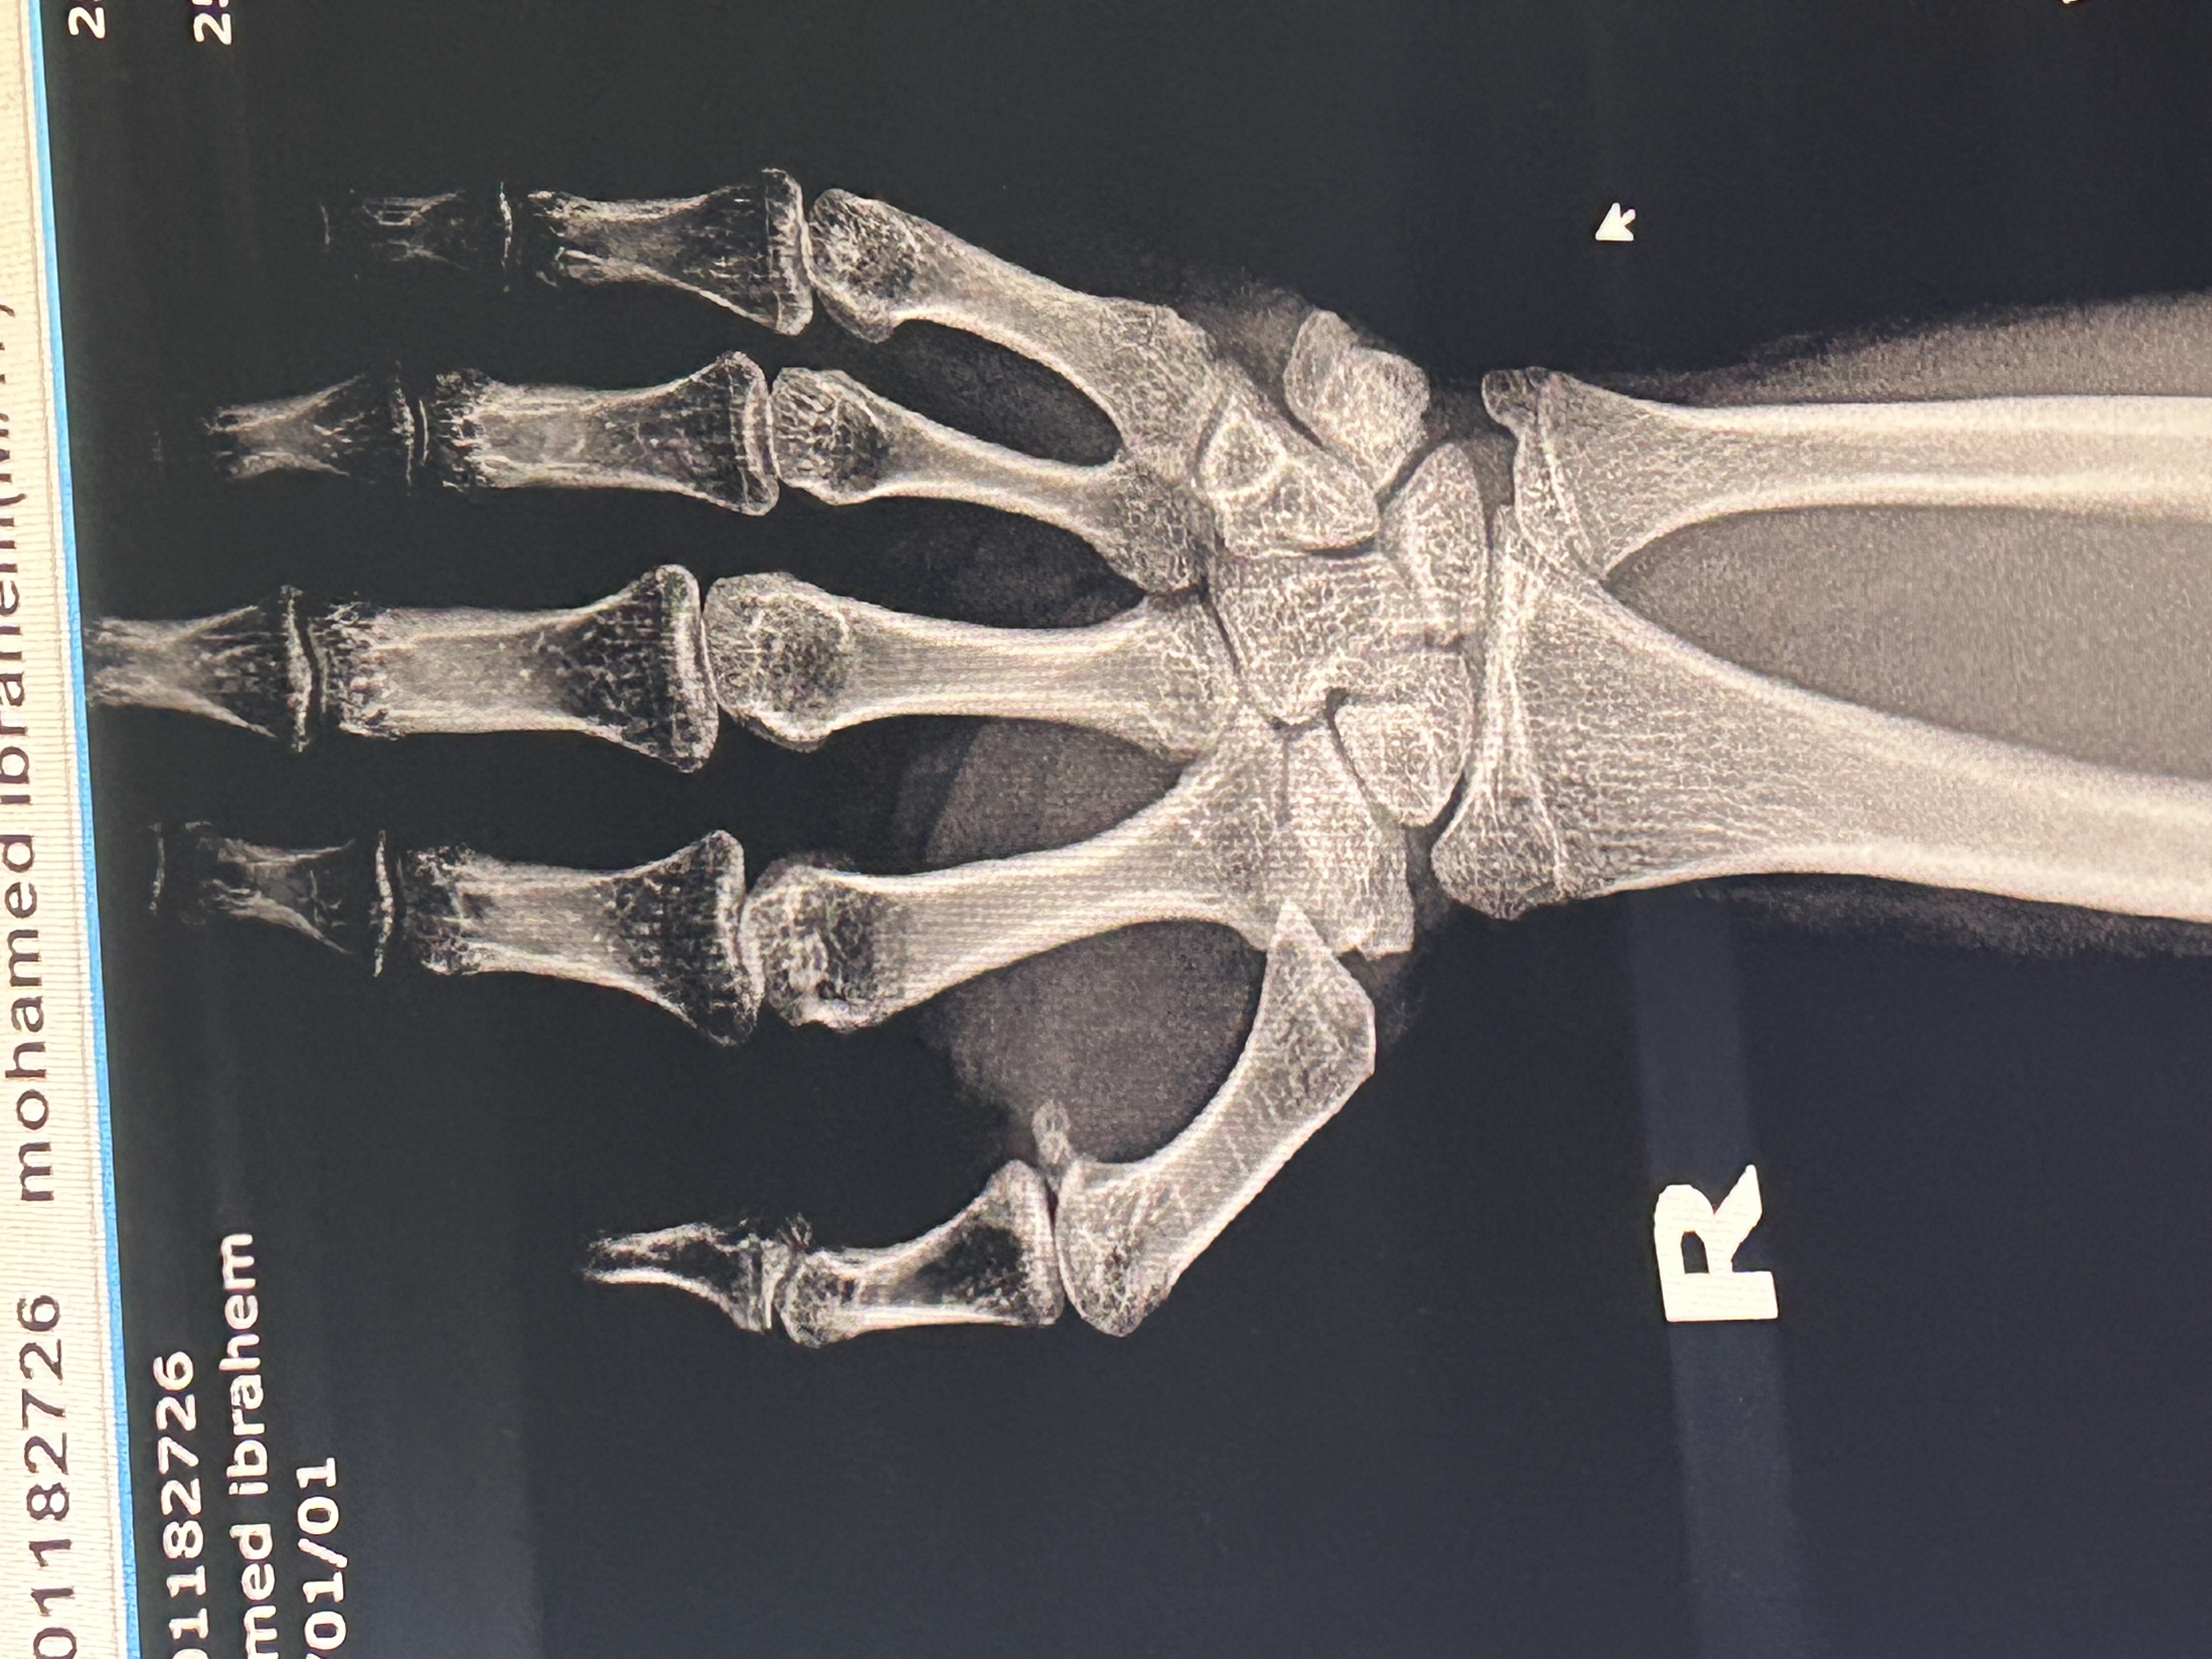

سقطت على يدي واصبح فيها الم وازرقت وانتفخت ولم اعد استطيع ان اغلقها او احرك اصابعي صورتها صورة اشعه والدكتور...